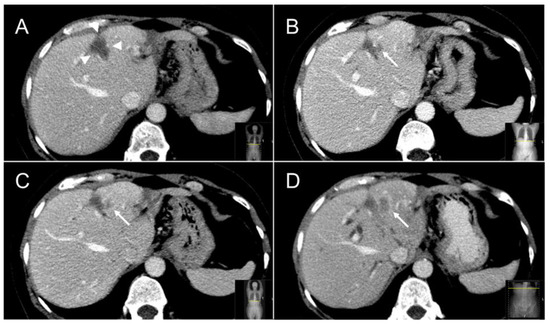

Figure 6.

Follow-up cross-sectional ceCT images of a CRLM treated with thermal ablation. At six months a typical sharply demarcated hypoattenuating scar lesion (white arrowheads) is visible (A). At 12 months a characteristic “incomplete ring sign” (white arrow) at the left margin of the ablation zone can be appreciated (B), which, especially when combined with 18F-FDG avidity, is highly specific for local tumor progression following thermal ablation. Follow-up ceCT at 15 and 18 months (C,D) further confirmed local tumor progression.